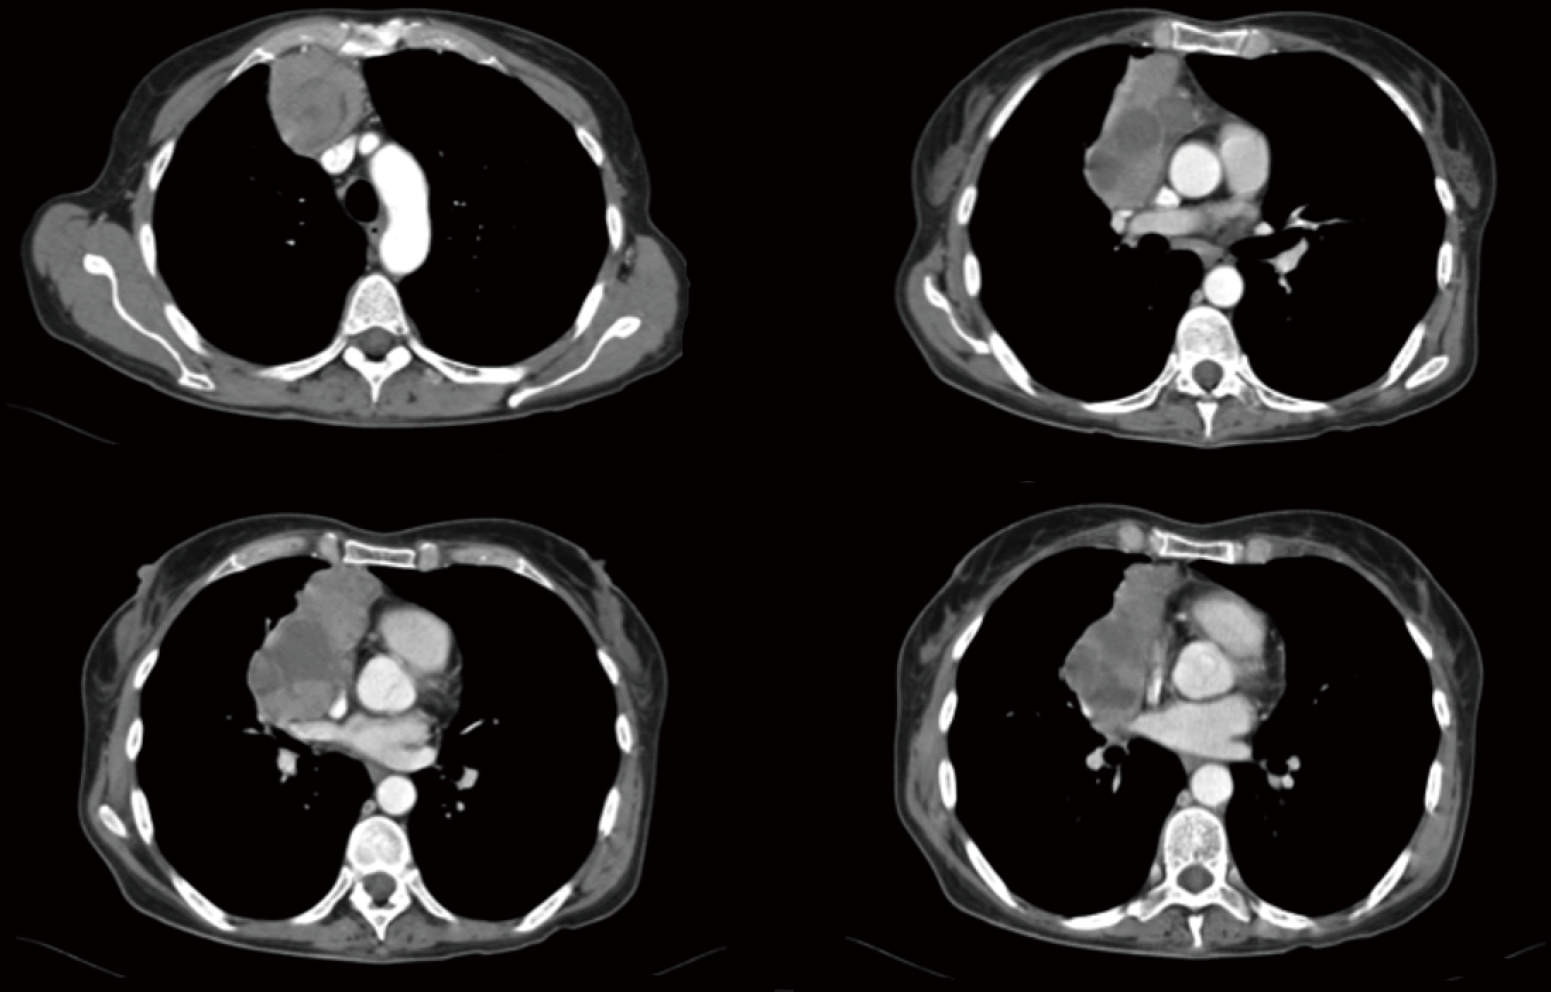

Extended resections of large thymomas importance of en bloc thymectomy Thymectomy Disease a thymectomy is the surgical removal of the thymus gland, which has been shown to play a role in the development of myasthenia. A thymectomy is done when someone has an autoimmune condition called myasthenia gravis or a tumor on the thymus called a thymoma. Surgeons perform a thymectomy to treat certain autoimmune diseases and cancers. thymectomy is. Thymectomy Disease.